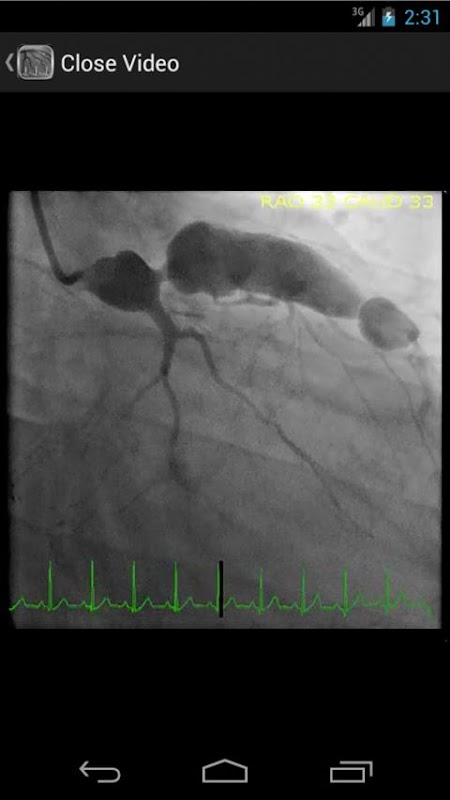

* قاعدة بيانات يمكن البحث فيها تحتوي على أكثر من 30 أشرطة الفيديو (تصوير القلب التاجية، ventriculograms، وaortograms) كل من استنتاجات مشتركة ونادرة في مختبر قسطرة القلب